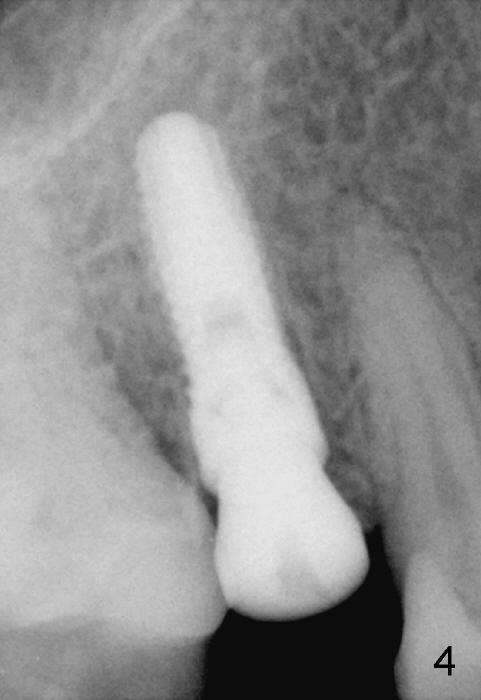

A 51-year-old man has several missing teeth in the maxilla restored by a partial denture. The tooth #4 fractures (Fig.1) and is planned to be restored by an implant (Fig.2 design: 4.5x14 mm). Immediately post extraction, osteotomy is initiated by a 2.0 mm pilot drill at the depth of 14 mm (3 mm into new bone, Fig.3). Finally a 4.5x14 mm SM (submerged) implant is placed with insertion of a 5.2x5(3) mm healing abutment (Fig.4). Mixture of autogenous bone and demineralized cortical allograft is placed in the gap between the buccal plate and the implant/abutment (Fig.6), covered by collagen membrane (Fig.7 M; P: partial denture). In fact the membrane is fixed between the implant and the healing abutment lingually. The wound is finally covered by perio dressing (Fig.5 ^). The patient returns 5 days postop. The perio dressing is removed unintentionally. It appears that the membrane has started to be resorbed (Fig.8).